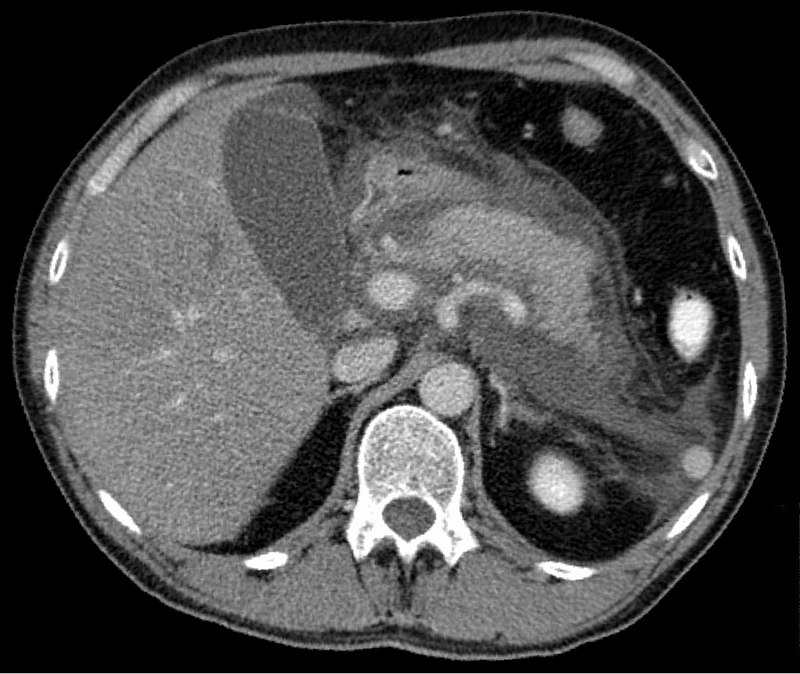

Chronic Pancreatitis

Chronic pancreatitis is the fibrosis of pancreatic parenchyma.

The most common cause of chronic pancreatitis is recurrent acute pancreatitis.

Imaging of chronic pancreatitis typically shows:

- Dystrophic calcification of the pancreatic parenchyma

- Chain of lakes appearance brought on by pancreatic duct enlargement